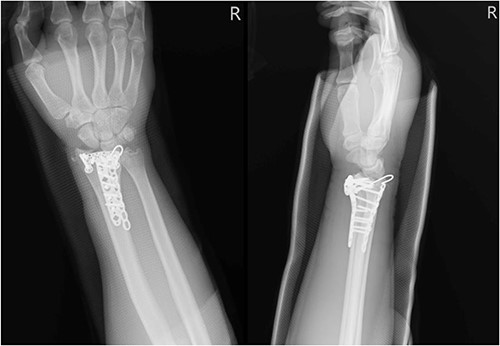

A 68-year-old female with underlying diseases of dyslipidemia, hypertension and a history of left distal radial fracture status post open reduction internal fixation on 4 April 2021, presented to our plastic surgery OPD on October 2022 with complaints of limited left thumb flexion for the past month. She reported experiencing sudden pain in her left forearm and left wrist radial site while pulling grass at home. On examination, she was found to have poor flexion of the left thumb, which was suggestive of a rupture of the FPL tendon. Left wrist X-ray showed fracture over radius with compression plate fixation (Fig. 3). After thorough discussion with the patient, it was decided that she would undergo tendon repair surgery.

Left wrist X-ray showing a fracture over the radius with compression plate fixation.